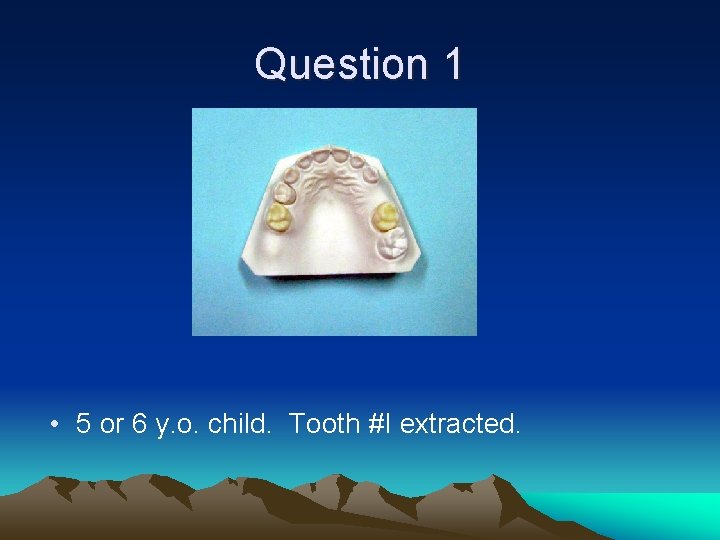

Question 1 • What tooth was extracted? How old is this child? • What is the appropriate space maintainer? • Will it have to be replaced with a different space maintainer in the future? If so, with what?

Question 1 • 5 or 6 y. o. child. Tooth #I extracted.